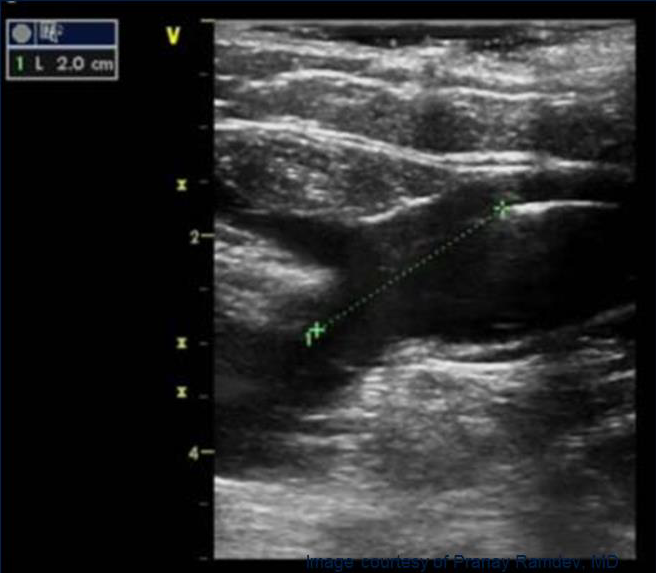

• Глубину залегания вены (< 10 мм от поверхности кожи)

• Минимальный и максимальный диаметры вены

Оптимальное расположение кончика катетера - на 2 см дистальнее СФС

ФИНАЛЬНЫЙ КОНТРОЛЬ ПОЛОЖЕНИЯ КОНЧИКА КАТЕТЕРА

Под контролем УЗИ убедитесь, что кончик катетера расположен на 2 см дистальнее СФС